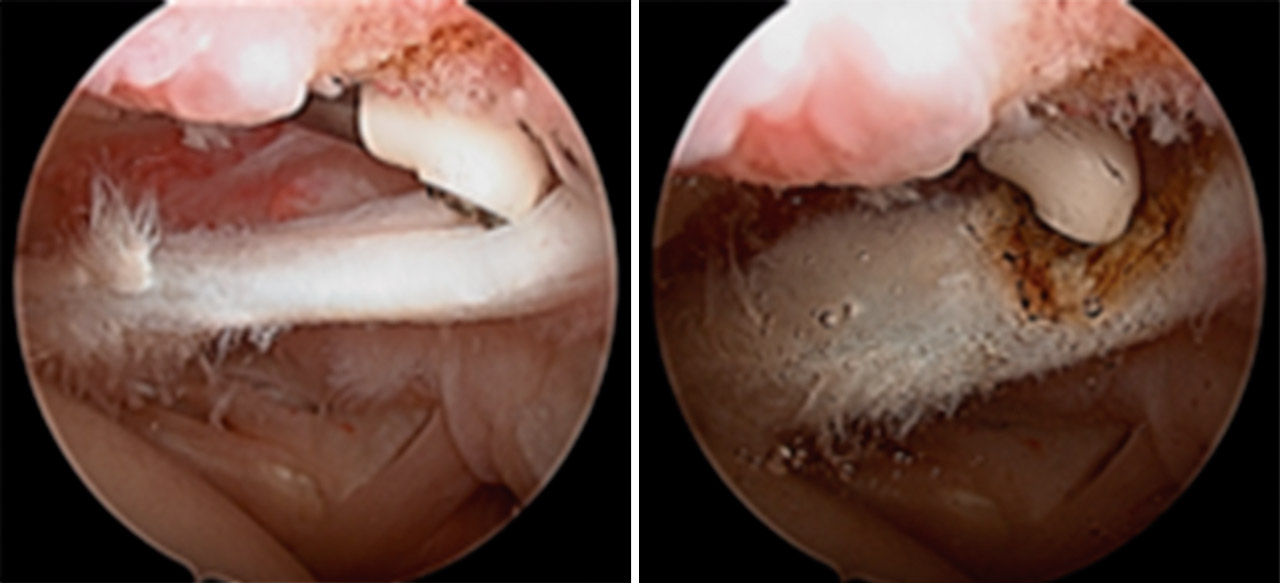

A la exploración física se evidenció movilidad completa, maniobras negativas para lesión de manguito de rotador o patología de articulación acromioclavicular. La exploración física fue positiva y compatible con lesión de SLAP (superior labrum anterior to posterior), confirmada con la artrorresonancia magnética (artro-RM) y diagnosticada como SLAP de tipo II; se programó para reparación artroscópica (Figura 1).

Se inició la artroscopia mediante el portal A habitual (Figura 3) y a través del portal E se confirmó la lesión de SLAP de tipo II con el gancho palpador (Figura 4). Confirmamos la laceración de la porción intraarticular del músculo bíceps braquial (Figura 5). Se realizó el portal D de trabajo para insertar un anclaje y comenzar a realizar la tenodesis de la porción larga del músculo bíceps braquial (PLB). En ese momento, el paciente presentó una grave inestabilidad hemodinámica que obligó a su colocación en decúbito supino y a despertarlo de la anestesia general. En esa posición, se decidió efectuar una tenotomía de la PLB para salvar el procedimiento (Figura 5).